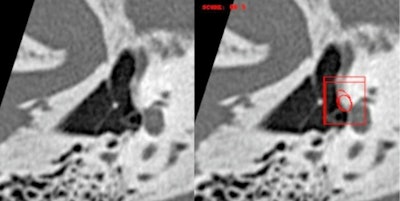

Regarding imaging, deep learning already allows clinical applications ranging from the automatic segmentation of anatomical structures, recognition of small pathologies such as otosclerosis, through to medical education, and even surgical planning with, in particular, facial nerve tracking. For otosclerosis, real performance results are at least equivalent to expert radiologists, even at stages I and II, also allowing differential diagnoses such as stapedial malformation or chronic otitis.

In a study using the algorithm developed using Cleverdoc tools and led by Oto-Med, the results of external validations of 124 cases studied on multibrand CTs, with otosclerosis confirmed surgically (Figure 2), were 96.6%, 95.3%, 95%, and 97% respectively for sensitivity, specificity, positive predictive value (PPV), and negative predictive value (NPV). The other tools developed relate to malformative and cholesteatoma pathologies and vestibular MRI. The future also lies in the integration of other biomarkers, whether clinical, biological, electrophysiological, anatomopathological, or genomic, to improve patient care.